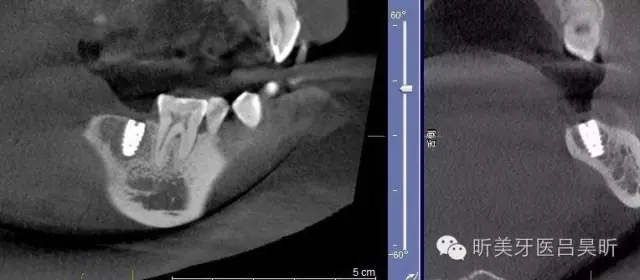

術(shù)前CBCT截圖,垂直骨量似乎感覺良好

可見種植位點舌側(cè)區(qū)凹陷,牙槽骨上部舌傾明顯。